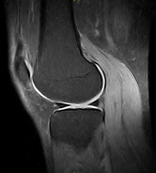

Left / Right Knee